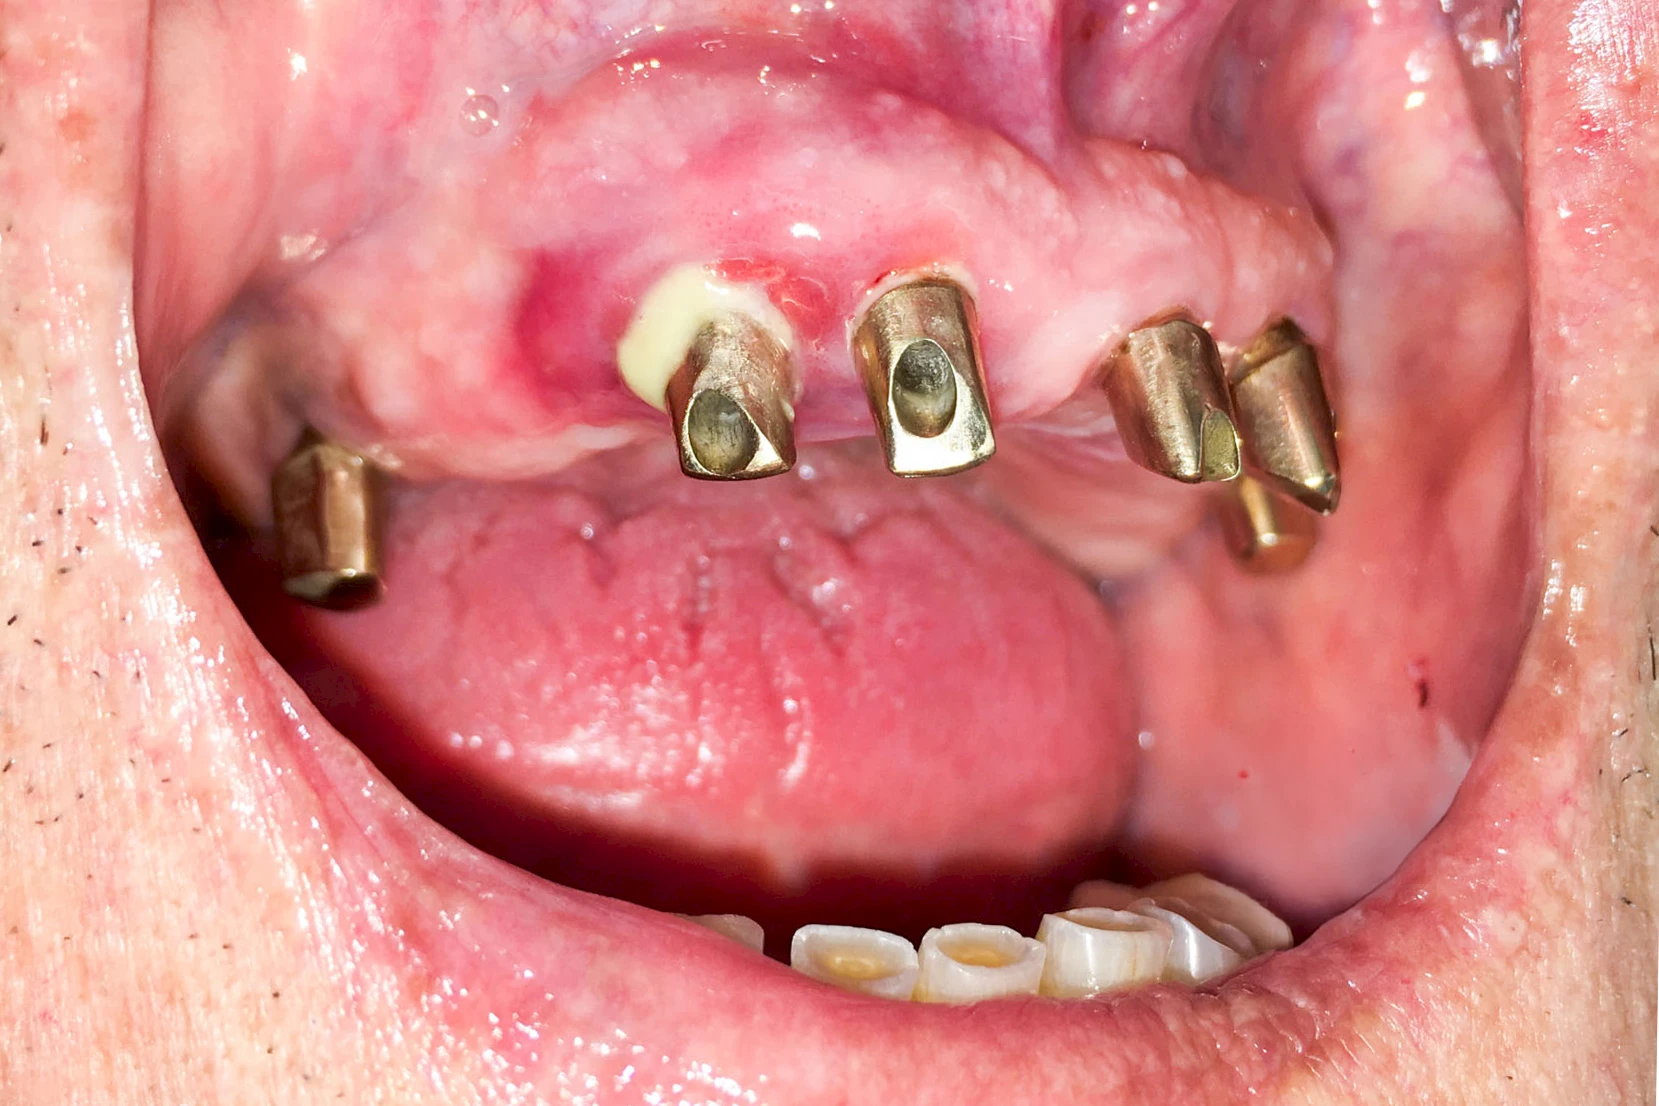

Diese Vermehrung von Bindegewebe in einem frei gewordenen Raum ist eine Sonderform der Anpassungsreaktion menschlicher Zellen und wird als Vakatwucherung bezeichnet.

Früher wurden im Unterkiefer mitunter Brücken zum Ersatz fehlender Zähne als sogenannte "Schwebebrücken" gestaltet. Die Idee dabei war, dass man die Brücke insgesamt besser reinigen kann. Allerdings war das für die Patienten mitunter irritierend für die Zunge und vor allem beim Essen gewöhnungsbedürftig. Teilweise haben sich hier reaktiv Vakatwucherungen der Kieferkammschleimhaut gebildet und den Raum unter der Brücke wieder verschlossen.